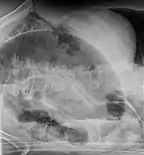

| Coronal CT of the abdomen, demonstrating a volvulus as indicated by twisting of the bowel stock | |